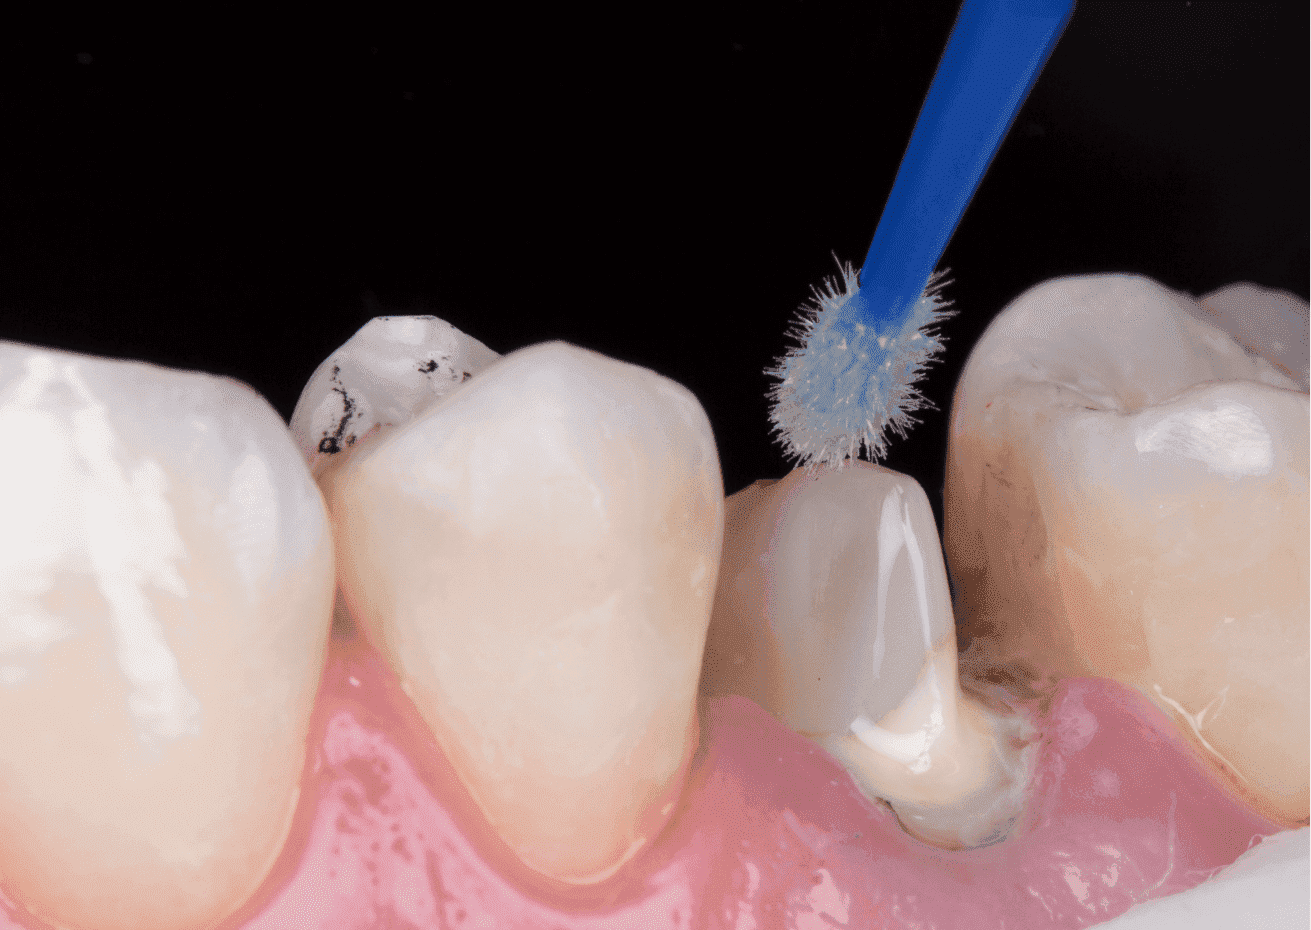

No planejamento reabilitador, foi reabilitado com dois pinos Whitepost SYSTEM cimentados com a combinação de sistema adesivo Ambar Universal APS e cimento resinoso dual Allcem CORE, que também foi utilizado para construção do núcleo de preenchimento.